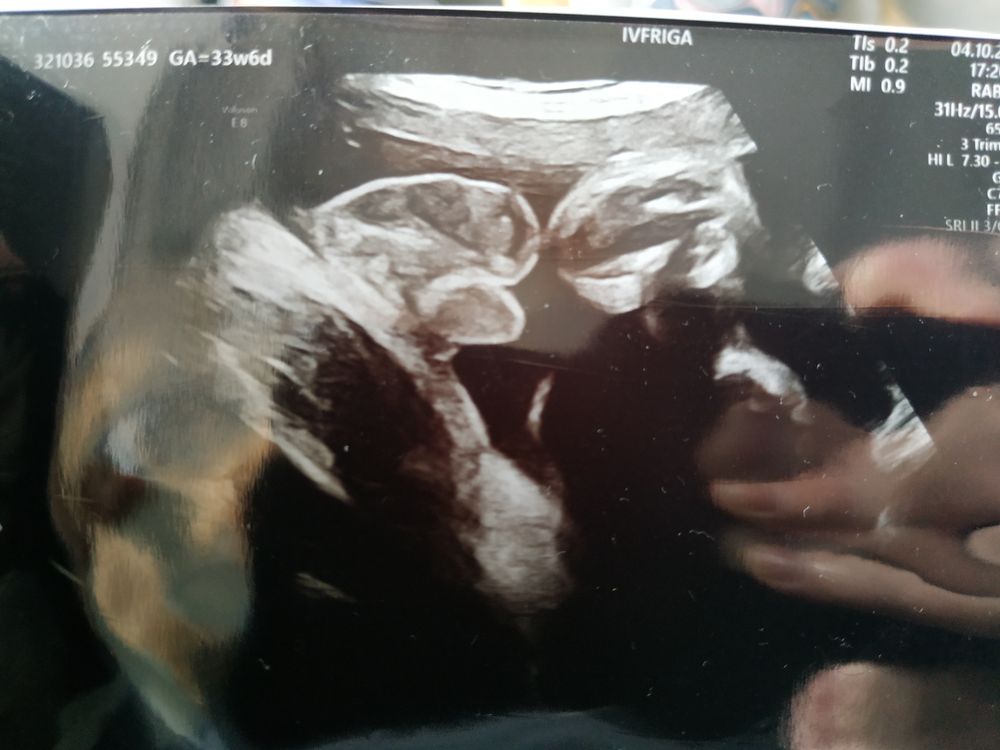

вот пример когда всё понятно и видно. Чёрный фон

Little Koldynia, я понимаю, на моем узи предоставлены только снимки гениталий🙈

В 37 недель такого черного фона быть просто не может, так как ребенок не помещается полностью на узи.